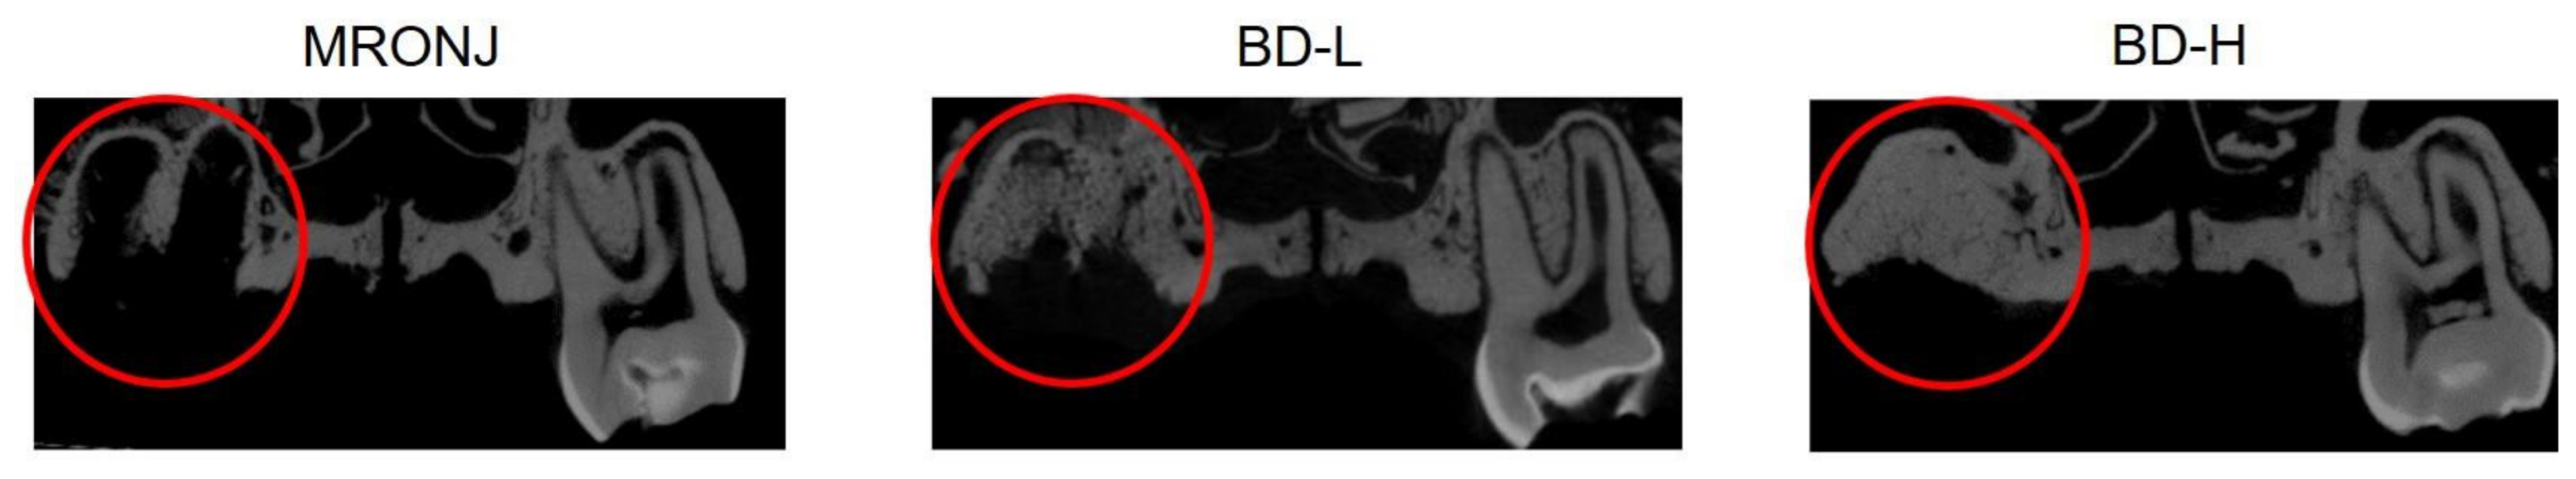

2. Results

3. Discussion

4. Materials and Methods